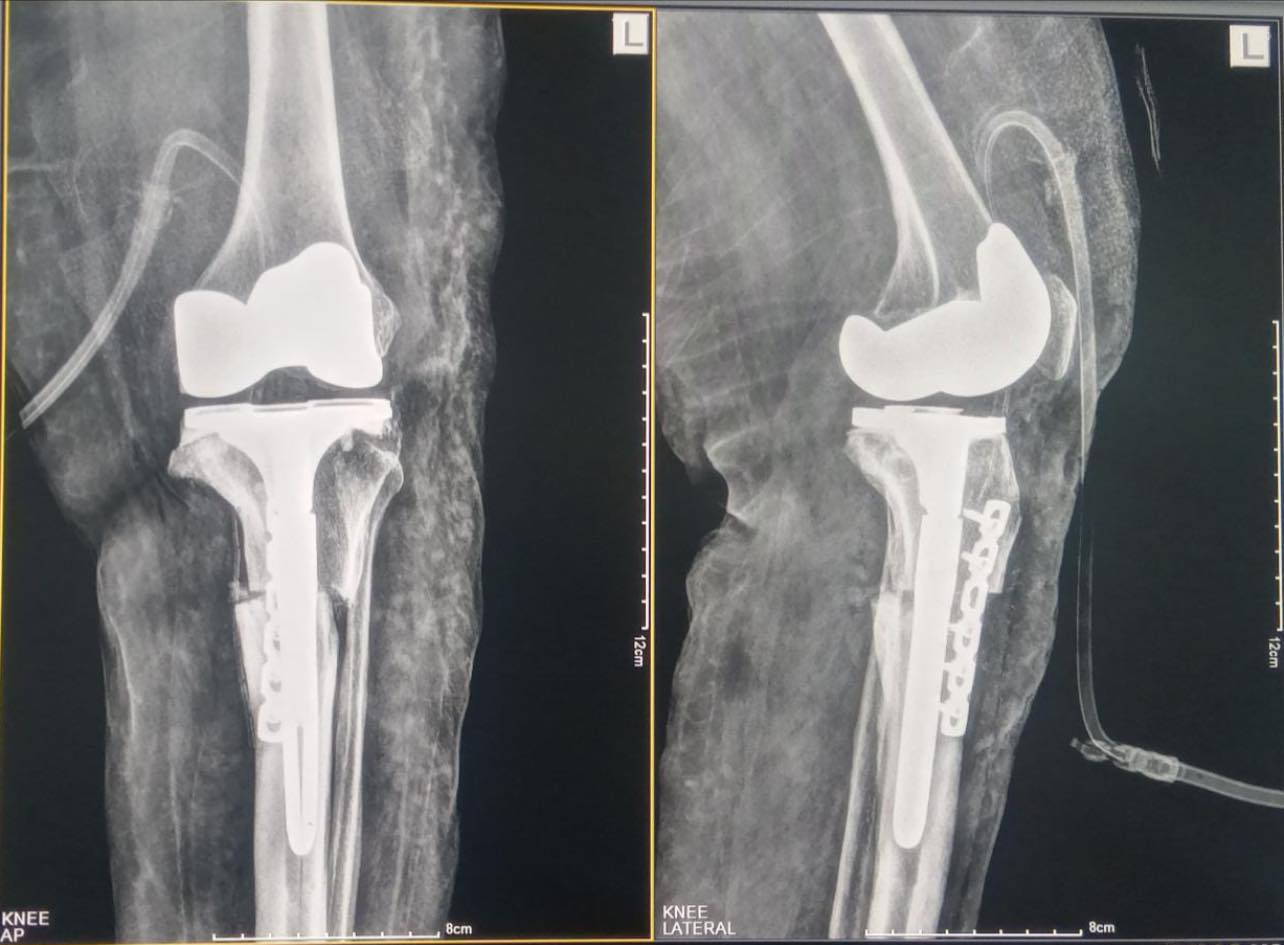

A 57-year-old female with ol malunited tibial plateau fracture and OA knee. In such cases just replacing the knee joint will not suffice as the deformed leg will cause continued pain and eventual failure of the surgery. The osteotomy straightens the leg deformity which is stabilized with this long stem prosthesis and outside recon plate.